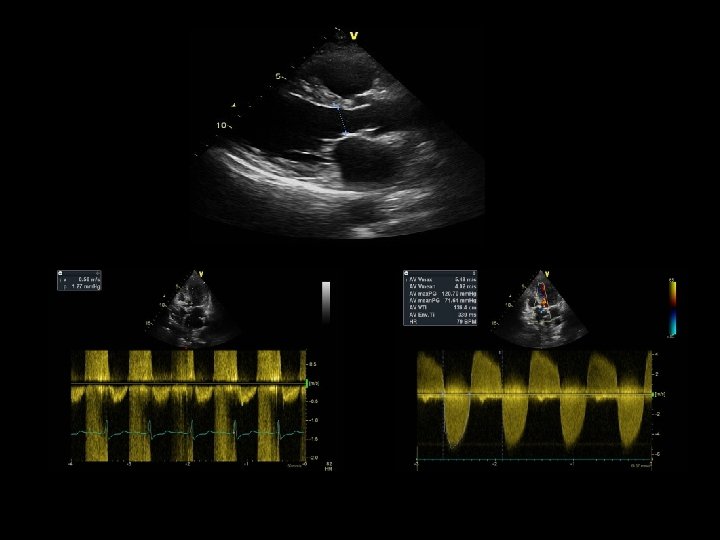

SEVERE AS Mean gradient = 71 mm Hg Dimensionless index = 0. 5 / 5. 5 = 0. 1

V 1 = 1. 5 m /sec V 2 = 4 m / sec DI = 1. 5 / 4 = 0. 375